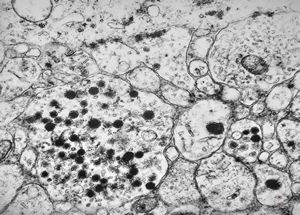

F,25y. | metachromatic leukodystrophy - n. suralis

F,8y. | metachromatic leukodystrophy - n. suralis

F,25y. | metachromatic leukodystrophy - n.suralis